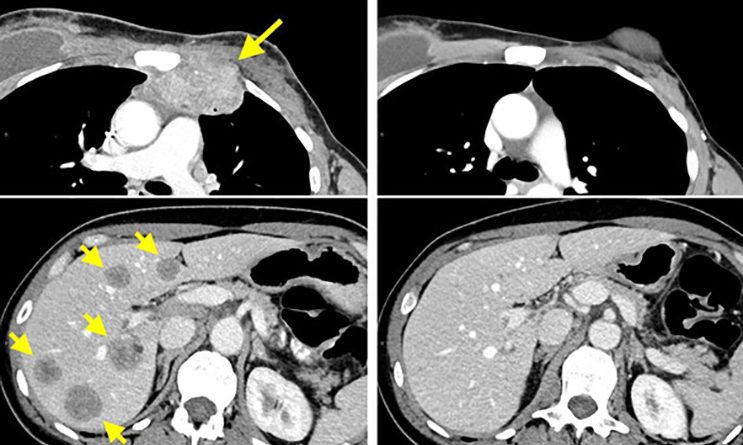

En este trabajo, los científicos aislaron y reactivaron las células T de esta paciente cuyo cáncer de mama metastásico estaba progresando a pesar de las terapias utilizadas. Estas células T reactivadas eliminaron todas las lesiones metastásicas, dejando libre de enfermedad a la mujer tras dos años desde el tratamiento.